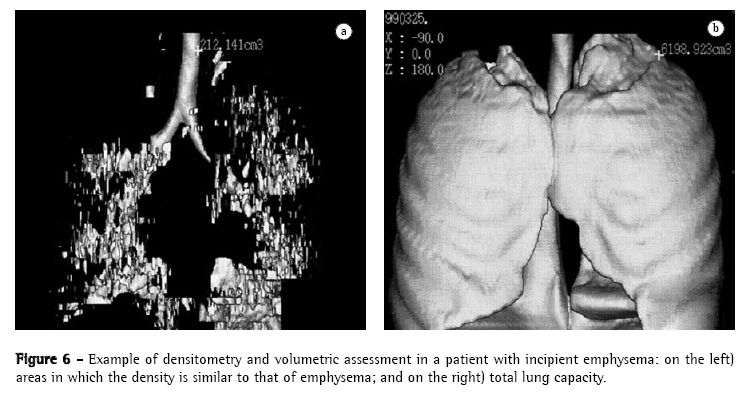

The acquisition of data volume in one single breath-hold allows us to calculate total volumes of normal lung and emphysematous areas, or emphysema-like, based on the density measured using Hounsfield scale. This technique is generally described as quantitative CT and could be better denominated as CT-guided pulmonary densitometry and volumetric assessment, since quantitative CT can be performed to measure area, not necessarily volume. Other authors have studied CT-guided pulmonary densitometry and volumetric assessment and have demonstrated the applicability of the method, when compared to traditional methods of detection and quantification of emphysema, such as spirometry, quantification by visual score and analysis by histograms.(40,51)

The acquisition of data volume in a single breath-hold allows us to reconstruct data in three-dimensional format, using three-dimensional CT. This technological resource has been more frequently used in the investigation of chest alterations.(51-56) One of the pioneers in the dissemination of the technique(56) demonstrated its efficiency in the quantification of emphysema. The denomination three-dimensional CT-guided densitometry and volumetric assessment for emphysema(55) has been currently suggested for this quantification process of the volume of emphysema, based on data obtained through spiral CT scan with three-dimensional representation of emphysematous lesions (Figures 5 and 6). The test measures the whole pulmonary volume with abnormal density and, also, the whole lung volume with normal density,(41,56-61) setting them apart based on the separation threshold generally selected at −950 HU, as per the suggestion of one author. Among the practical applications of the technique, one study demonstrated that normal CT-guided pulmonary densitometry and volumetric assessment excels HRCT, and should be included in the preoperative evaluation of patients for whom surgery for volumetric reduction of the lungs has been indicated.(58) This clinical applicability of three-dimensional CT-guided densitometry and volumetric assessment used for the same purpose has been known in Brazil for some time.(39) In a recent consensus, the use of three-dimensional CT-guided densitometry and volumetric assessment was suggested for the evaluation of therapeutic efficacy in the treatment of emphysema, replacing FEV.(59)

With the establishment of normality reference values,(55) it is already possible, as well, to use three-dimensional CT-guided densitometry and volumetric assessment in the early diagnosis and graduation of the severity of the disease, and this early detection and demonstration of three-dimensional imaging to the patient has been suggested as potentially useful in techniques of smoking cessation.(60) In addition, it also seems promising in the evaluation of patients whose occupational activities can induce the development of emphysema.